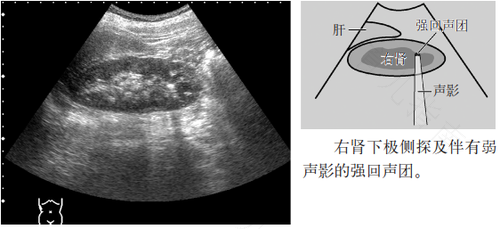

肾钙盐沉积是肾的病理性改变,是由于机体摄人维生素D的含量多而造成,导致肠胃吸收钙与磷增加、血钙浓度过高,当钙盐沉大部分积在肾脏的时候才会造成肾钙盐沉积。表现也会有许多:肾结石、夜尿增多、尿路异常,食欲不好、面色不好、等症状。